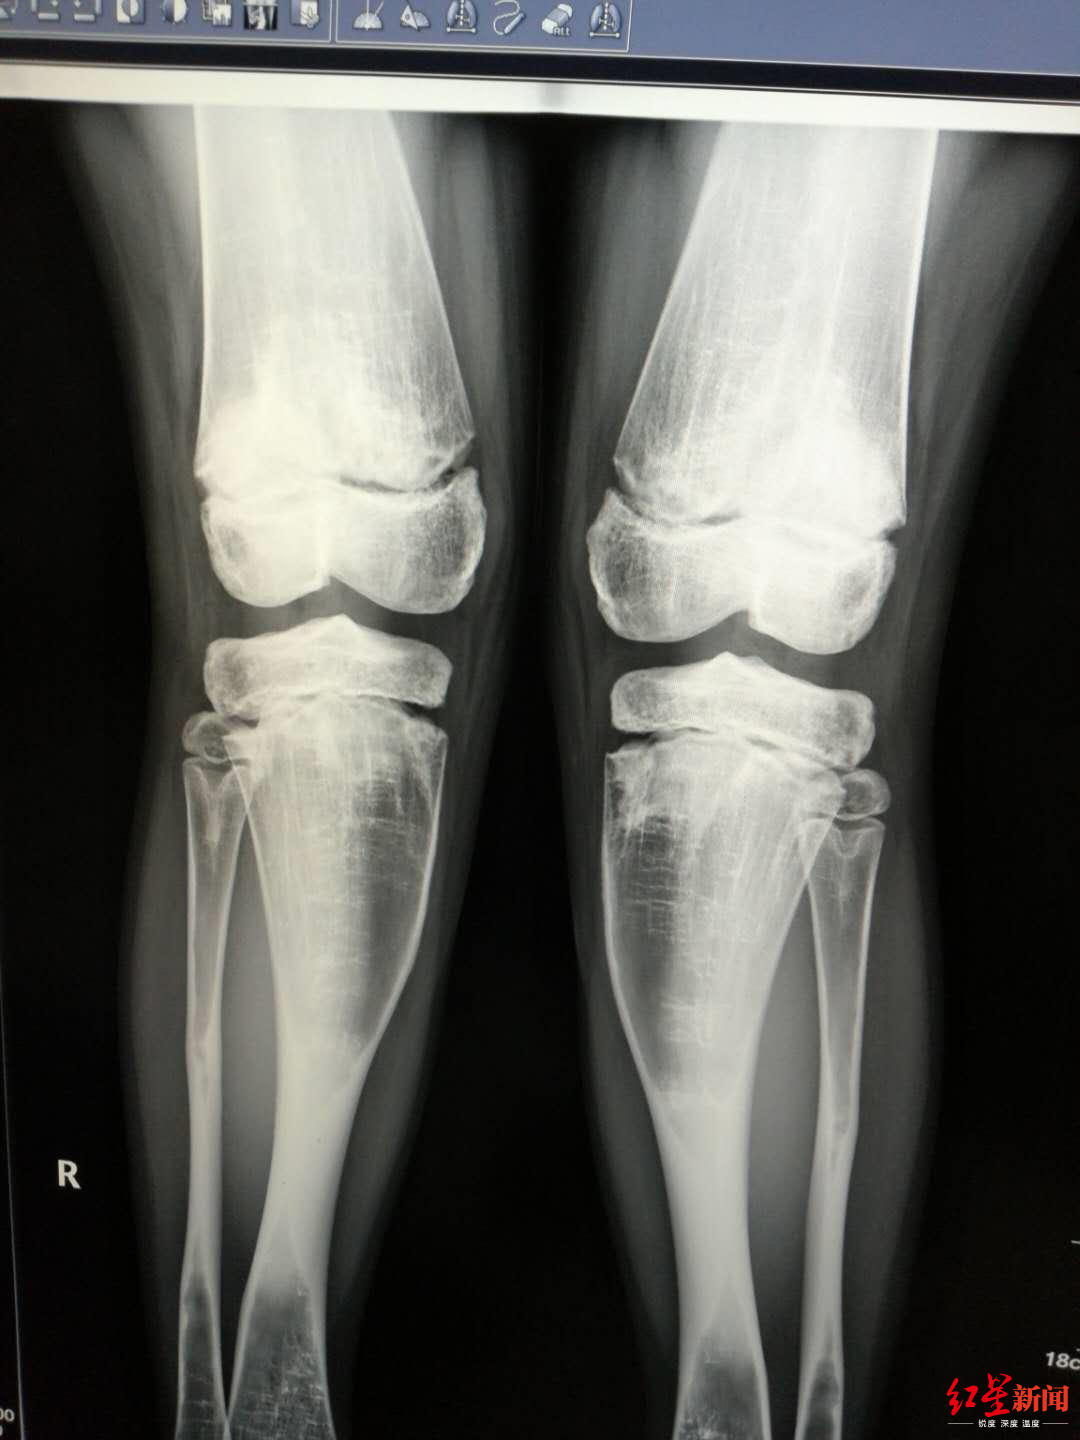

女孩鼻窦炎反复,医生发现竟是因为骨头

1080x1440 - 84KB - JPEG